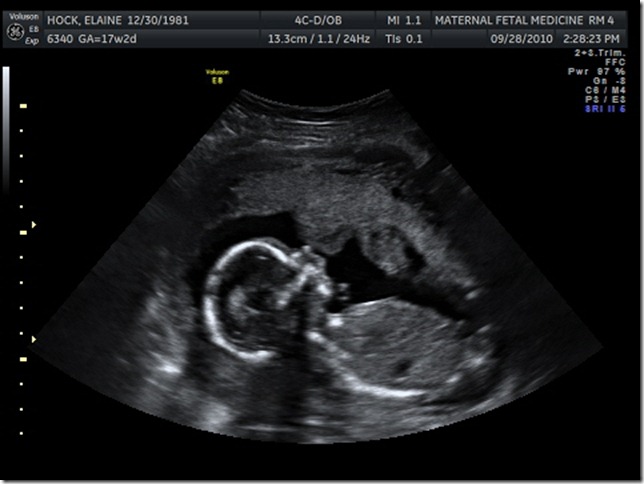

Pretty Profile!

Caleb is so happy to have a brother!  He giggled for at least 5 minutes after the lady told us it was a boy.  I am so happy that everything looked good.  No abnormalities or anything to be worried about.  Just another beautiful, healthy baby!  So far the head and stomach are measuring a little big- Caleb was the same way.  He is about 7 ounces now and in the 48th percentile overall.  I go back on Oct 27th for another scan and for an echo of his heart, which is protocol for me and my pregnancies.  Heart looked good though so I shouldn’t worry.  Caleb had a small spot of concern on his during that scan but it turned out to be fine.   It was another long day but a good one.  I got to watch my new boy move all around for about an hour and he is definitely a mover.  I just haven’t felt him for sure yet.  A few times I thought so but couldn’t tell for sure.  He was moving constantly.  Our tech said he was very cooperative.  I hope he stays that way!  I’m so excited to meet him now.